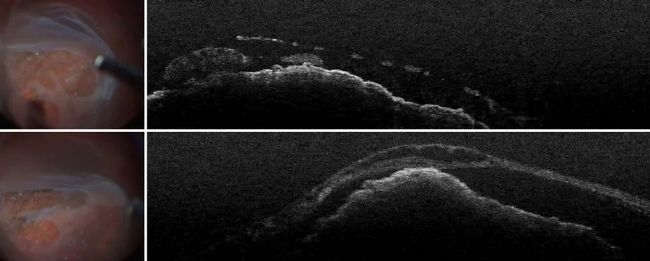

對患兒進行了全身麻醉,以便進行全面檢查。術中使用 OCT 觀察白色小葉,這在臨床上是無法做到的。成像顯示白色小葉位于視網膜下,與視網膜色素上皮粘連(圖 5)。這表明它不是視網膜腫瘤。它導致視網膜萎縮,一直延伸到內緣膜。

外科醫生認為這是纖維血管疤痕、纖維化脈絡膜新生血管(CNV),而不是腫瘤復發。

圖 5:術中 OCT 使白色小葉清晰可見,證實腫瘤沒有復發。圖片由 Nikolaos Bechrakis 教授提供。